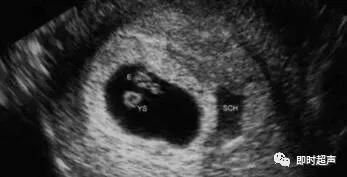

“新英格兰医学杂志”胚胎停育超声诊断标准:

1、头臀长度至少为7毫米,无心跳;2、平均孕囊直径至少25毫米,无胚胎;3、超声检查没有卵黄囊的孕囊,2周后,仍然没有发现有心脏搏动的胚胎;4、超声检查有卵黄囊的孕囊至少11天后,没有发现有心脏搏动的胚胎;超声检查满足以上任何一个标准的情况下,即可诊断胚胎停育。

此外,超声检查怀疑流产,但不能明确诊断的声像图如下:1、头臀长度小于7毫米,无心跳;2、平均孕囊直径16-24毫米,无胚胎;3、超声检查孕囊里没有卵黄囊7-13天后,未发现有心脏搏动的胚胎;4、超声检查有卵黄囊的孕囊7-10天后,没有发现有心脏搏动的胚胎;5、末次月经后至少6周没有发现胚胎;6、羊膜囊与卵黄囊相邻,未见胚胎;7、卵黄囊超过7毫米;8、孕囊与胚胎大小相比(平均孕囊直径和头臀长之间的差异小于5mm)。